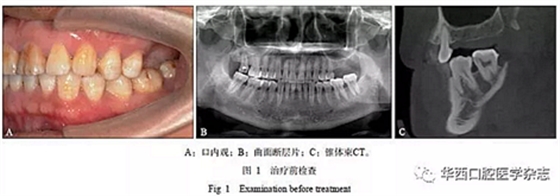

患者男性,45歲,2015年10月由四川大學(xué)華西口腔醫(yī)院種植科轉(zhuǎn)診,主訴“左上后牙缺失,種植前要求壓低左下后牙”??趦?nèi)檢查見上下牙列無擁擠,25與35牙為中性關(guān)系,26、27牙缺失,36、37牙伸長(圖1A)。

1)正畸治療前完善影像學(xué)檢查(圖1B、C)及牙周基礎(chǔ)治療;